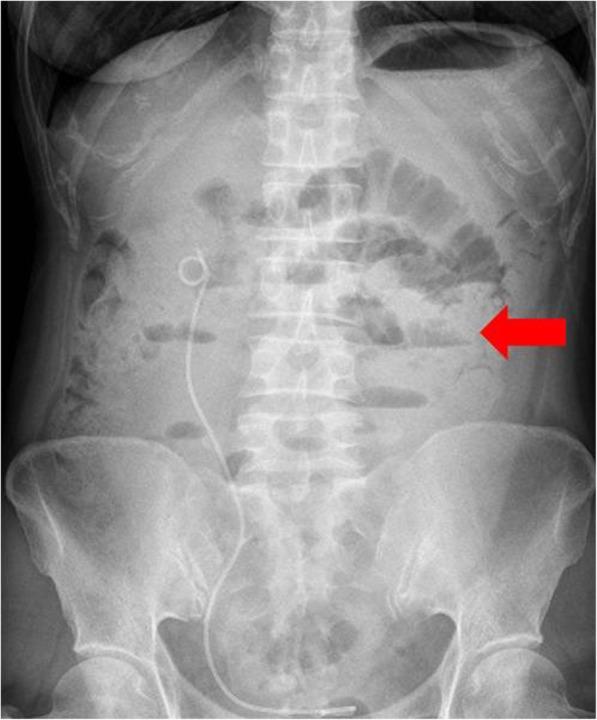

Three patients harbored gBRCAwt with low tumor load (LTL), while two women harbored BRCAmt with high tumor load (HTL) were recruited. Two of the three LTL patients achieved partial response, and the other showed stable disease. Both HTL patients were assessed to have progressive disease in a short time. Olaparib appears to be effective and safe for LTL recurrent ovarian cancer patients even if it is gBRCAwt, while the response is poor in HTL patients.

3 名患者携带 gBRCAwt 且肿瘤负荷低(LTL),而另外 2 名患者携带 BRCAmt 且肿瘤负荷高(HTL)。3 名 LTL 患者中有 2 名达到部分缓解,另 1 名表现为疾病稳定。两名 HTL 患者在短时间内均被评估为疾病进展。奥拉帕利似乎对 LTL 复发性卵巢癌患者有效且安全,即使它是 gBRCAwt,而在 HTL 患者中反应较差。